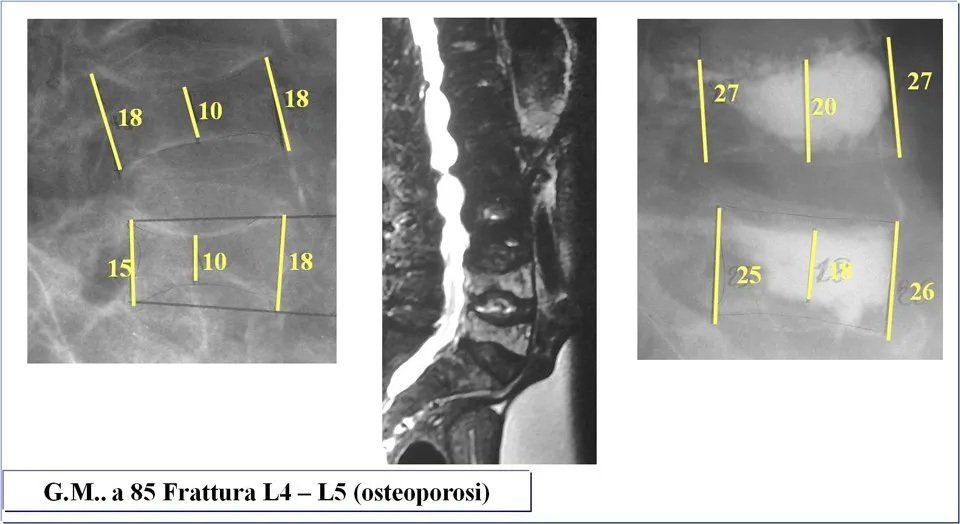

Il dottor Andrea Piazzolla rappresenta un sicuro punto di riferimento per i pazienti colpiti da una frattura vertebrale causata dall’osteoporosi. Presso lo studio medico di Bari è possibile eseguire una visita di controllo al fine di valutare l’effettivo stadio della frattura in atto, studiando la fragilità delle ossa, l’aspetto in termini meccanici, la deformità presentata e l’esatta sede della frattura. Questa prima diagnosi e valutazione è necessaria alla progettazione di una terapia adatta alla risoluzione di questo genere di problematica. Fissa oggi stesso un appuntamento presso lo studio medico situato in via Rodolfo Redi 3 a Bari: chiama per prenotare.

Generalmente le sollecitazioni che apportano un maggior effetto sul rachide in ortostasi sono rappresentate dalla forza di compressione, che è costante, e la forza flessoria che invece è variabile e che dipende dal momento flettente. Conoscere l’entità della cifosi contribuisce a comprendere l’intensità del movimento flessorio.